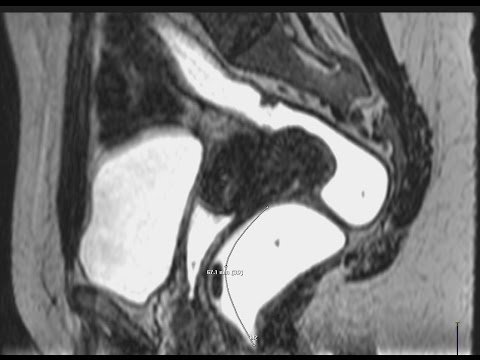

Hellow guys, Welcome to my website, and you are watching Discoid Bowel Resection For Recurrent Bowel Endometriosis. and this vIdeo is uploaded by Dr. Niteen Ghorpade Endometriosis Surgeon at 2022-04-27T09:14:09-07:00. We are pramote this video only for entertainment and educational perpose only. So, I hop you like our website.